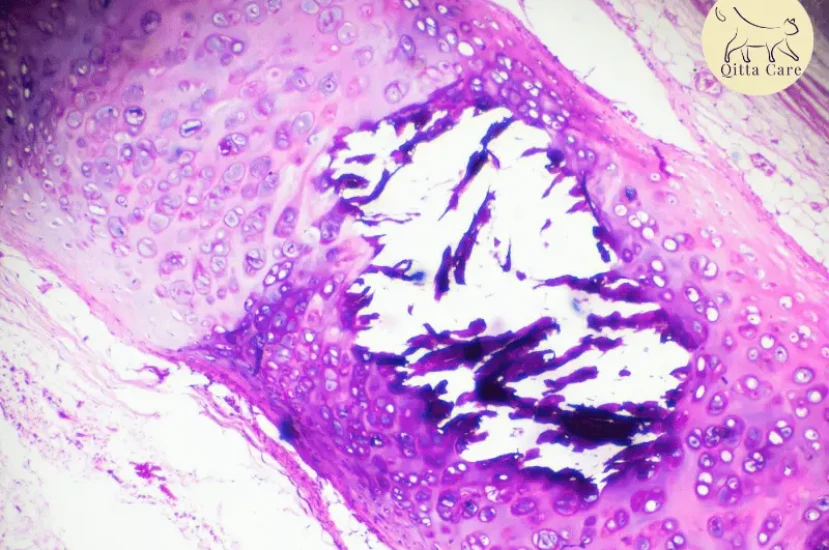

اسباب تراكم القيح داخل التجويف الجنبي

• العدوى: البكتيريا الموجودة عادةً في الفم (مثل Pasteurella multocida وBacteroides) وهي الأكثر شيوعًا، البكتيريا اللاهوائية الإجبارية (مثل Peptostreptococcus، Fusobacterium) شائعة.

• الطفيليات: Spirocerca lupi يعيش في العقيدات في المريء.

• الأورام أو السرطان: نادرًا ما يحدث مع الأورام في الصدر، نتيجة لموت نسيج الورم.

• التفاف فص رئوي: يرتبط أحيانًا بتراكم القيح في التجويف الجنبي.

• الأجسام الغريبة: تُوجد بشكل نادر، حتى مع الاستكشاف الجراحي.